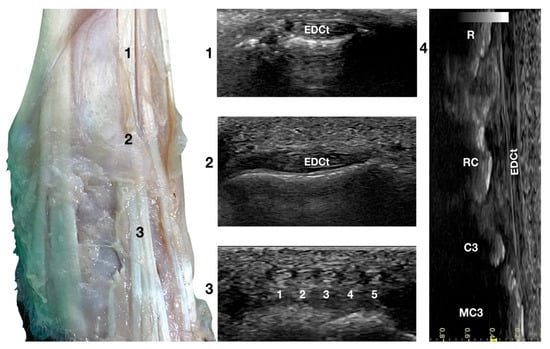

Just lateral to the groove of the Extensor Carpi Radialis tendon and lateral to the large accessory cephalic vein, in the more prominent but shallower Extensor Digitorum Communis groove, on the dorsal surface of the carpus, the Extensor Digitorum Communis tendon (EDCt) was palpated and easily visualised in a transverse scan plane (Figure 1a). At the ulnar notch level, the tendon is thin and flattened with a markedly oval shape and is easily recognised by the medially located, rounder, Extensor Carpi Radialis tendon (Figure 3).

Figure 3.

Dorsal carpal face centred on the Extensor Digitorum Communis tendon. At the ulnar notch level (2), the EDC tendon is thin and large, easily differentiated from the ECRt by its shape and position. Dorsally, just distal to the tenomuscular junction (1), the tendon is thicker and narrower. At the level of the radiocarpal joint (3), the tendon subdivides into four small tendons (white 2 to 5). The small, medial tendon of the Extensor Digiti I Longus is often visible (white 1). On the longitudinal scan plane (4), the fine fibrillar pattern of the thin tendon is visible. The image shows the part of the tendon that crosses the radius (R), the radiocarpal bone (RC), the carpal bone three (C3), and the third metacarpal bone (MC3).

In a transverse scan plane, sliding the probe proximally, the EDCt became rounder and thicker at the tenomuscular junction. Sliding the probe distally, the EDCt was enclosed in a common synovial tendon sheath and passed through the lateral distal sulcus of the radius. The Extensor Retinaculum was seen as a thick hyperechoic line. Most of the time, this structure was ultrasonographically indistinct from the tendon sheath. The Extensor Retinaculum surrounded the tendon and blended with the periosteum on the lip of the carpal articular surface. At the level of the radiocarpal joint, the uniformly flattened EDCt divided into four separate thin tendons. They passed on the dorsal surface of the corresponding digits, ending in the dorsal portion of the ungual crest of the distal phalanges. With the 18 MHz probe, it was possible to differentiate the small tendons clamped together from the intercarpal joints and which became more distinct structures when progressing distally.

The tendon of the Extensor Digiti I Longus was inconsistently seen medially. In this case, five small tendons were seen running distally on the dorsal surfaces of the metacarpal bones. The tendon thickness reduced sharply at the subdivision, and the distal portion of the tendons was often too thin to be visible on the transverse plane. At the same time, it was possible to see its termination on the longitudinal scan planes when the patient’s paw was elevated from the ground and the digits were extended. The tendons were thin, having a straight path and the typical fibrillar pattern. The extension and flexion of the digits helped to define the tendon insertion and assess tendon function, lesions, adhesion, and subluxation.